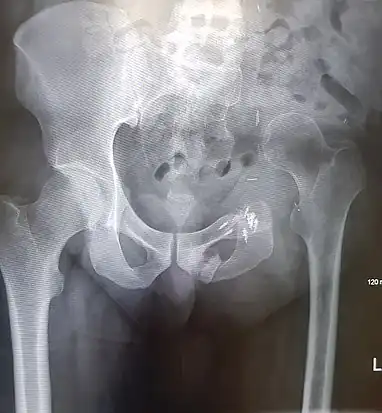

- An x-ray of a limb-sparing hemipelvectomy on the left side of a male pelvis taken one month after surgery.

- An x-ray of the same pelvis taken eighteen months after surgery highlighting the femur migration to its final resting place.